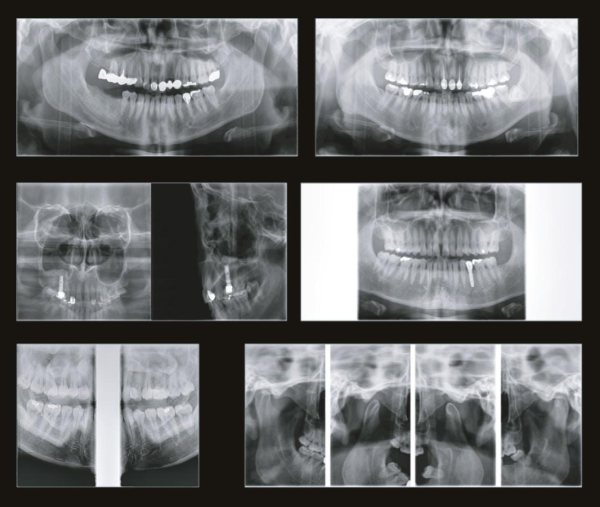

Металл больше не помеха

Зачастую частицы металла портят результаты сканирования. Однако с новой технологией SMARF об этой проблеме можно забыть. Умная система убирает помехи от излучения металла, делая картинку четкой и подробной. Благодаря ей у вас на руках будет вся необходимая диагностическая информация.

Металл больше не помеха

Зачастую частицы металла портят результаты сканирования. Однако с новой технологией SMARF об этой проблеме можно забыть. Умная система убирает помехи от излучения металла, делая картинку четкой и подробной. Благодаря ей у вас на руках будет вся необходимая диагностическая информация.